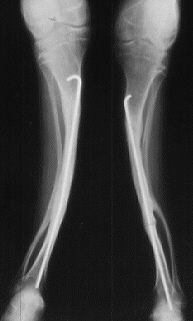

A 18-years-old boy. Body height 114cm. Sillence type III.

The first visit was at 4 years of age. He sustained 16 fractures in L/E and 30 fractures in U/E. He underwent 9 operations. He had 80 degrees progressive scoliosis and recently underwent posterior spinal fusion with internal instrumentation. He obtained his initial gate at 18 months of age, and had been practical ambulator until 9 years old. However, the diameter of the femur which was 15mm at 7 years of age had started to decrease prior to the functional aggravation. He eventually became a non-ambulator after the ankle joint fracture at 9 years old. The diameter of the right and left femur at the age of 18 were 7 and 8 mm respectively.